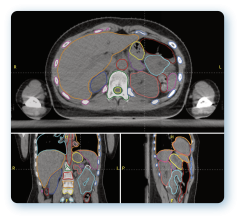

Varian Medical Systems will be exhibiting its complete line of hardware, software, and applicators for HDR and LDR brachytherapy, including the VariSource iX, GammaMedplus iX and the GammaMedplus 3/24 iX HDR afterloaders, the BrachyVision treatment planning system plus the Vitesse module for using transrectal ultrasound (TRUS) images as the basis for a prostate cancer treatment plan. For LDR treatments, the VariSeed treatment planning system is a leading system for this highly specialized form of brachytherapy.